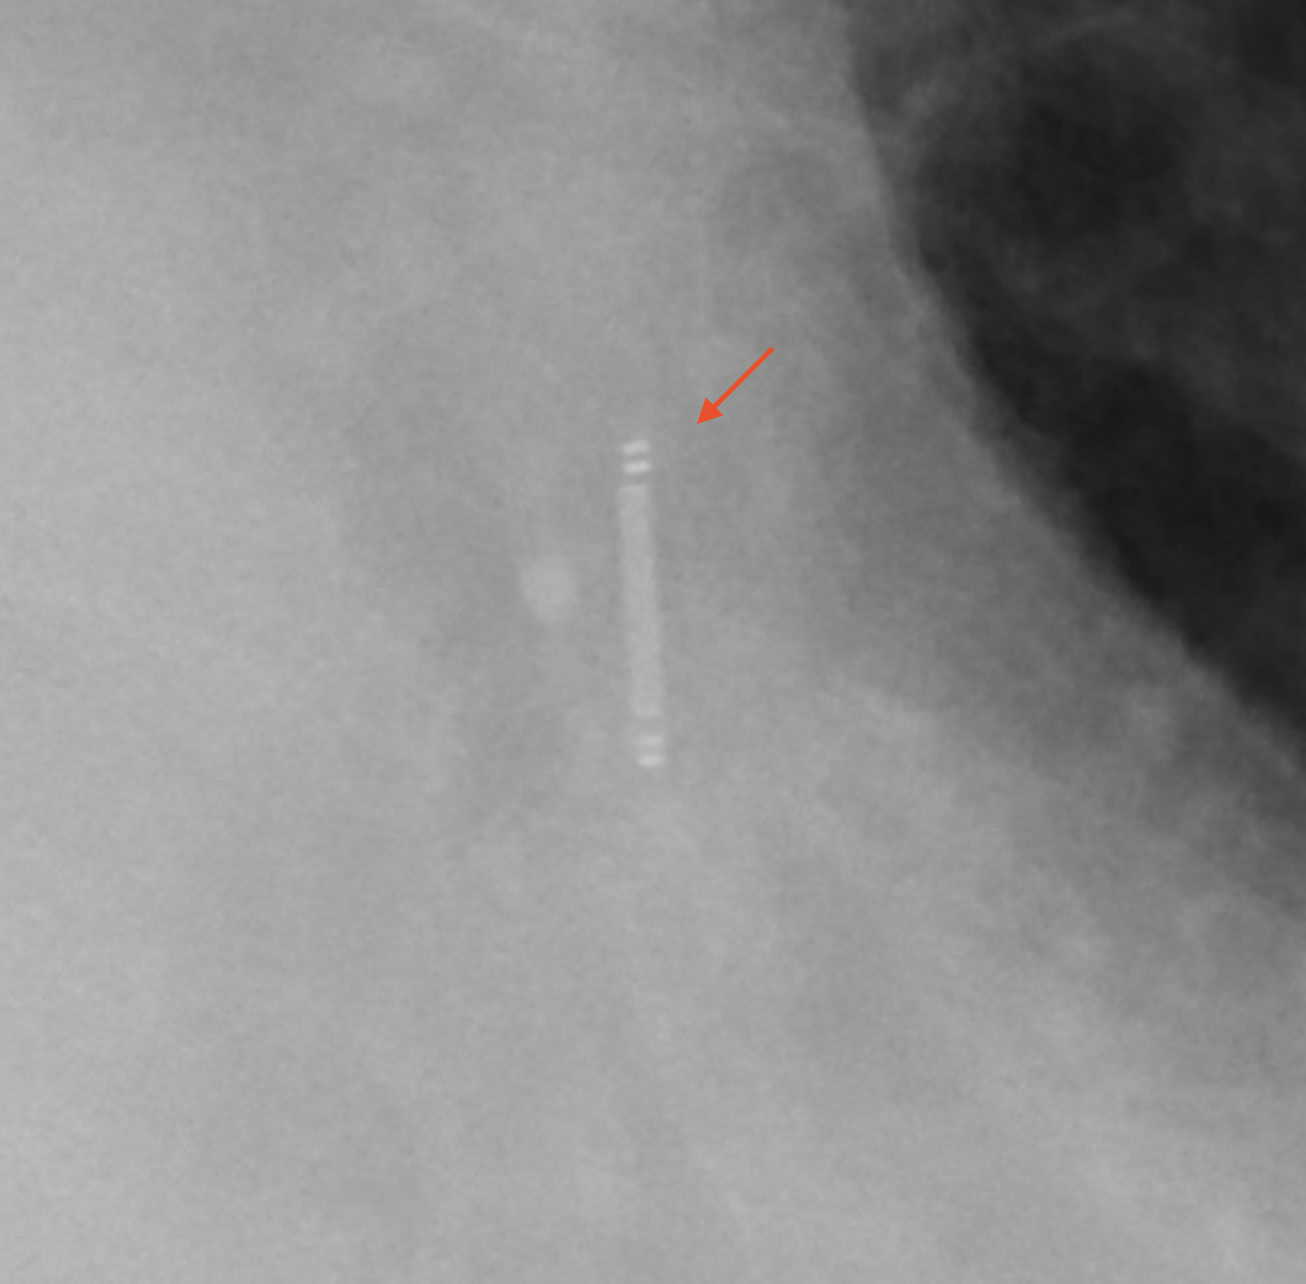

Radiographic Appearance

Note the Presence of the CardioMEMS Superimposed Over the Left Pulmonary Artery in the Following Chest X-Ray (and Inset)